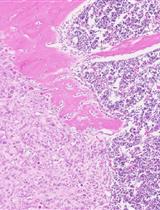

Various genetic alterations such as chromosomal translocation cause leukemia. For examples, gene rearrangements of the mixed-lineage leukemia (MLL) gene generate MLL fusion genes, whose products are potent oncogenic drivers in acute leukemia. To better understand the mechanism of disease onset, several murine leukemia models using retroviral gene transduction, xenograft, or Cre-mediated chromosomal translocation have been developed over the past twenty years. Particularly, a retroviral gene transduction-mediated murine leukemia model has been frequently used in the leukemia research field. Here, we describe the detailed protocol for this model.

Gene rearrangements generate mixed-lineage leukemia (MLL) fusion genes, which cause highly aggressive acute leukemia. MLL-rearrangements are often associated with few additional genetic alterations and poor clinical outcomes (Andersson et al., 2015). Wild-type MLL enhances and maintains the expression of a subset of genes, including homeobox (Hox) genes, to stimulate the expansion of immature progenitors (Jude et al., 2007). The expression of Hoxa9 and Meis1 is highest in the immature progenitor/stem cell fraction, but gradually declines as cells differentiate, and eventually diminishes in terminally-differentiated cell fractions (Somervaille and Cleary, 2006; Yokoyama et al., 2013). The MLL fusion protein constitutively up-regulates the expression of target genes, including Hoxa9 and Meis1, to immortalize immature progenitor cells and cause leukemia in vivo (Ayton and Cleary, 2003; Lavau et al., 1997). To date, more than 130 different MLL-rearrangements have been identified (Meyer et al., 2017). Two-thirds of MLL-rearranged leukemia cases are caused by fusion with a gene that is part of the AF4 family-ENL family-P-TEFb (AEP) complex (Yokoyama et al., 2010). The MLL fusion proteins constitutively form an MLL/AEP hybrid complex on the target chromatin (Okuda et al., 2014; Yokoyama et al., 2010), which further associates with the SL1 complex to activate RNA polymerase II-dependent transcription (Okuda et al., 2015 and 2016). AEP-mediated transactivation of MLL target genes transformed myeloid progenitors ex vivo, but did not cause leukemia in vivo, which suggested that other function is additionally required for in vivo leukemogenesis (Okuda et al., 2017). Recently, we showed that the ability to recruit the DOT1L complex is necessary to cause leukemia in vivo in addition to the ability to recruit AEP using in vivo leukemogenesis model. Thus, the combinatorial use of the in vivo leukemogenesis model and myeloid progenitor transformation assay is necessary to dissect the functional properties of oncogenes. In this protocol, we describe the in vivo leukemogenesis model using retroviral transduction in detail.